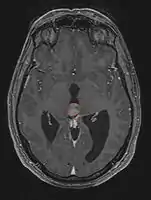

Pineal Gland Tumors

Clinical Presentation

- Determined by the spatial anatomy and direction of growth

- Obstruction of aquaduct: hydrocephalus presenting as headaches, nausea, vomiting

- Compromise of superior colliculus: vertical gaze palsy, pupillary and oculomotor nerve paresis (Parinaud syndrome)

- Progressive growth: cranial nerve neuropathies, hypothalamic dysfunction